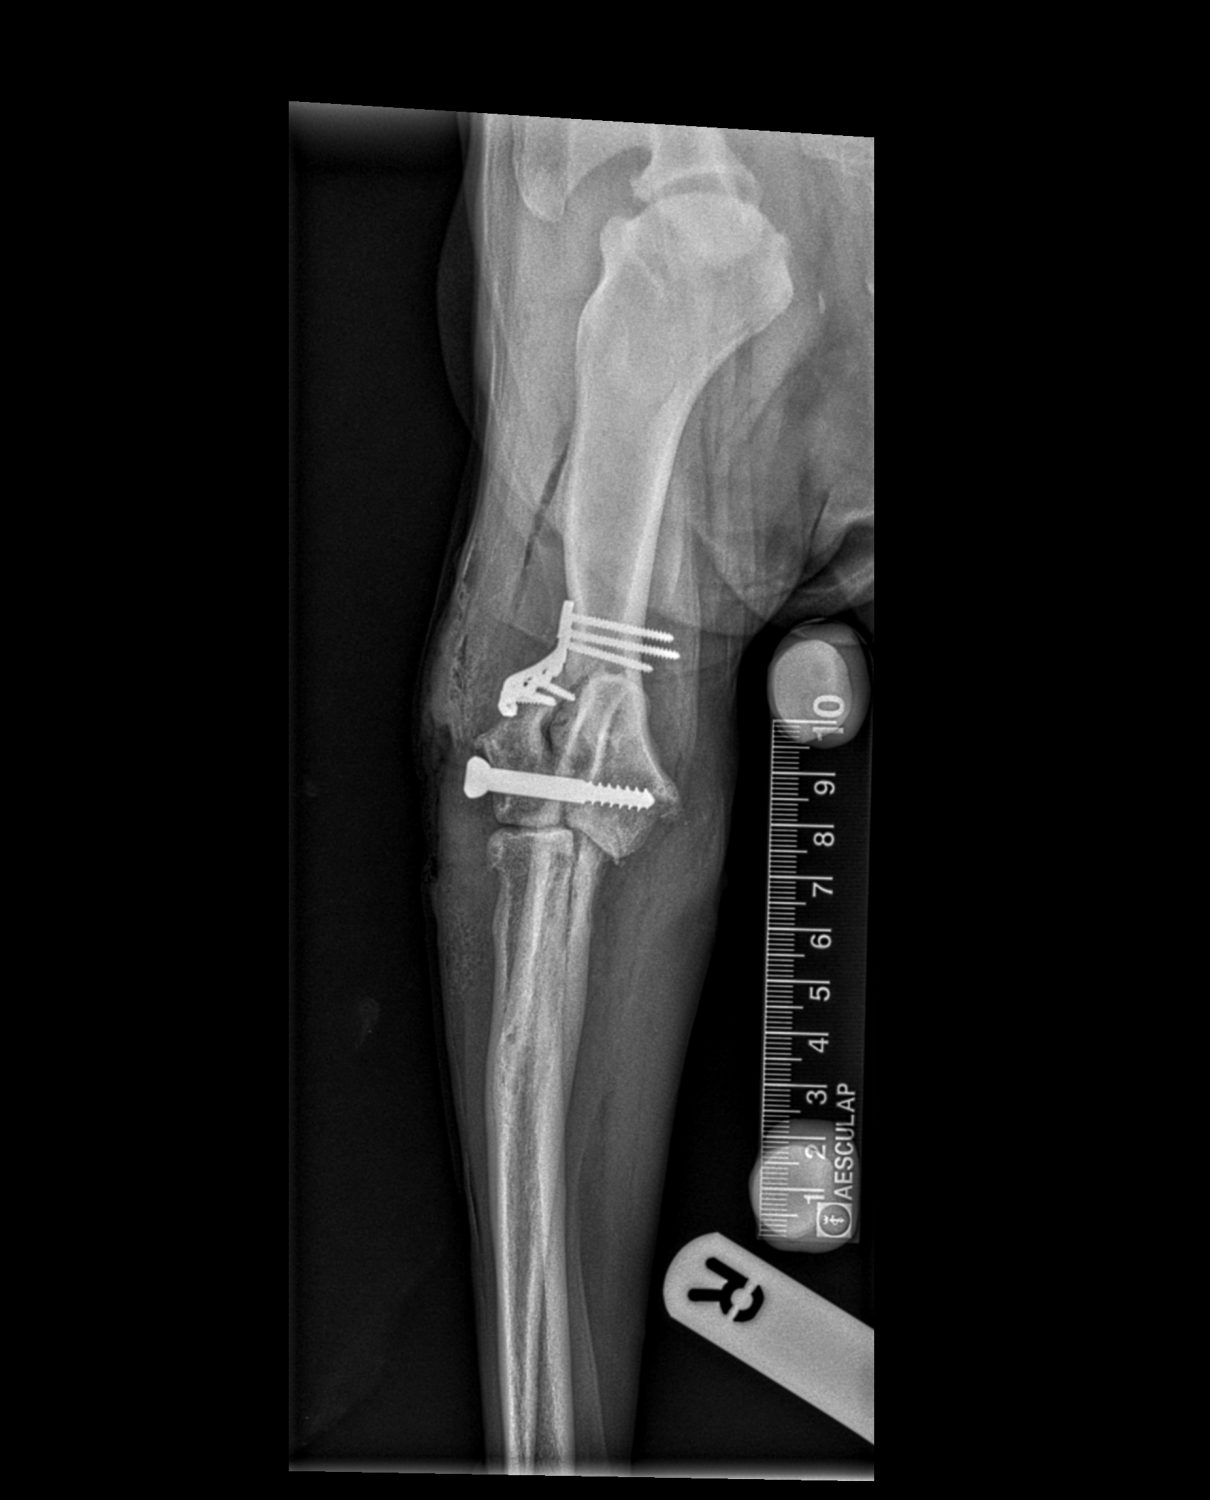

Chase is a  twelve-year-old English Springer Spaniel, with a history of severe arthritis in his elbows, presented lame in the right elbow after sustaining an injury whilst jumping into the car. X-rays revealed a humeral intracondylar fissure that had fractured.

Surgical repair was required, and this was performed by practice principal Dr Martin Hobbs and senior veterinary surgeon Dr Rupert Davenport. A CT scan was carried out prior to the surgery to assist with pre-surgical planning. After incision, the fractured bone was manipulated back into a normal anatomical position, and secured in place using plates and screws. The site was closed using dissolvable sutures, and post-operative x-rays confirmed the surgery had been successful.